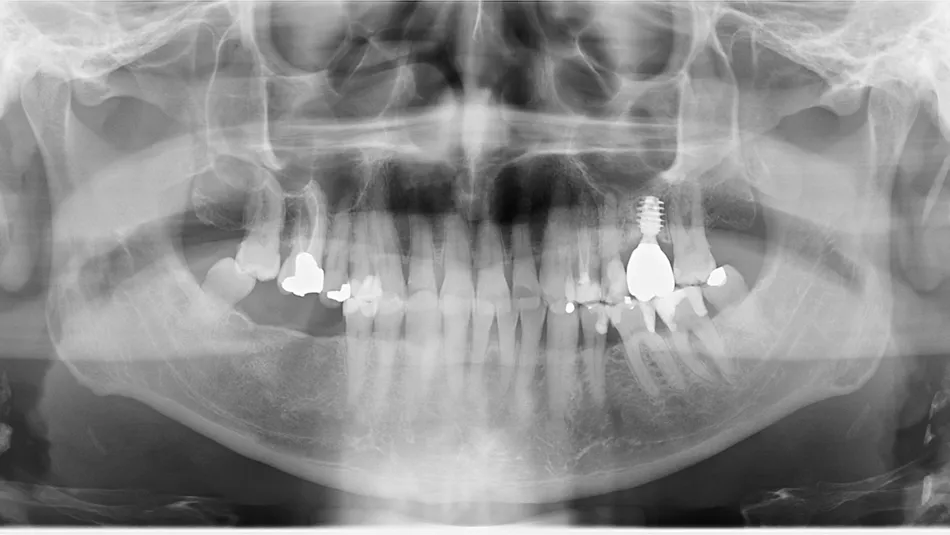

The patient was diagnosed by 3D CT scan and radiograph during a routine control of a classic first molar.  The clinical signs necessitated tooth extraction followed by immediate implantation, socket gap filling and placement of a sealing socket abutment to support anatomical structures.

1. Radiograph of initial situation.

4. Radiograph exhibiting a suitable septum for immediate implant placement.

4